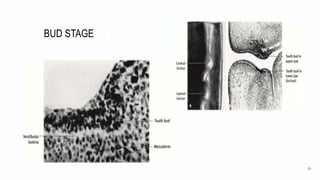

Bud Stage

• Enamel organ has

- peripheral low columnar cells

- central polygonal cells.

• Cells undergo mitosis and condense by:

- increased mitotic activity

- neural crest cells migration into the area.

Developmental Stages3

• Bud Stage (cont’d)

At this stage:

dental papilla is the area immediately adjacent to enamel organ.

dental sac is the condensed ectomesenchyme that surrounds tooth

bud and dental papilla.

Both dental papilla and the dental sac become well-defined and grow

into cap and bell stages.